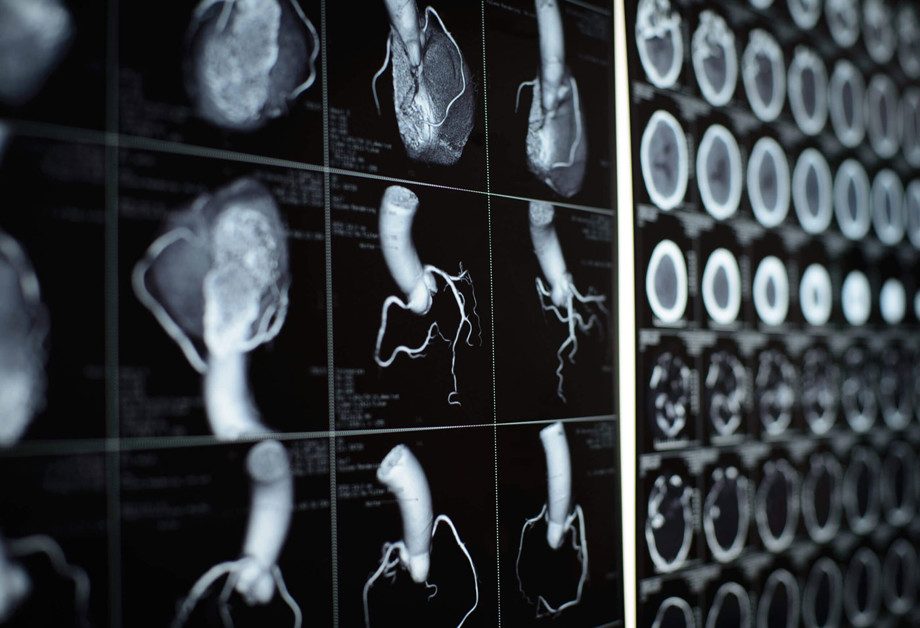

CTCA is a specialised type of CT scan that is used to detect narrowing of the coronary arteries that may affect blood flow to the heart muscle causing chest pain (angina), or that may increase the risk of a heart attack. CTCA differs from a CT Calcium Score in that it can detect non-calcified cholesterol deposits in the arteries that may narrow the vessel but are also possibly at risk of causing sudden vessel blockage (heart attack) without treatment.

As the heart is in almost constant motion, we require your heart rate to be at a certain level to enable motionless images of the heart vessels. This will depend on various factors such as your blood pressure, general medical condition, and any specific cardiac conditions. The supervising radiologist or cardiologist on site will determine what is appropriate and safe for you. Preparation may take up to 90 minutes.

The test itself is relatively quick and involves cannulation, spray or tablets under the tongue to dilate the vessels, injection of contrast (X-ray dye), and short periods of holding your breath.